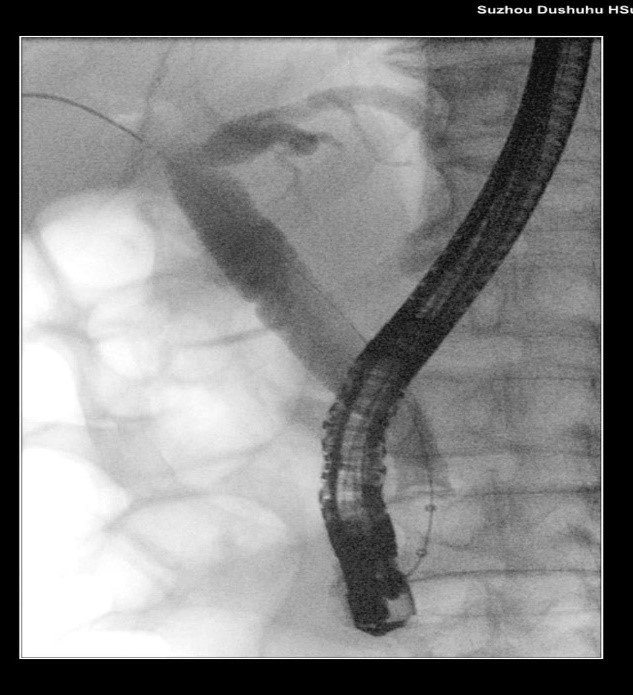

苏大附四院ERCP团队在手术中看到陈大爷的胆总管在结石的影响下已经宽达13mm,结石大小11*10mm,将十二指肠乳头切开并扩张后用取石球囊把结石取出,置入胆管支架使胆汁充分引流,顺利解除了胆道梗阻。

扩张取石

取石前后